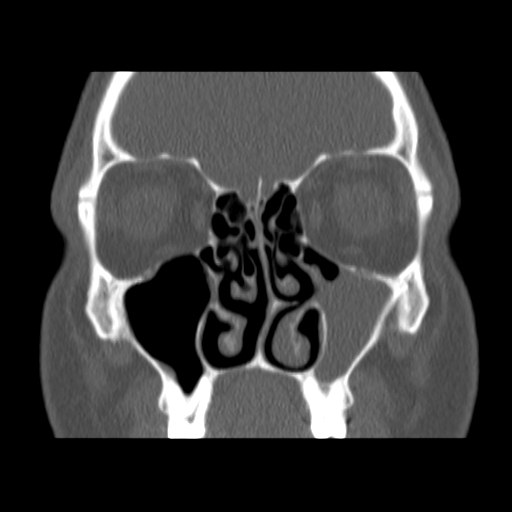

Here are a few shots illustrating how off-kilter my septum is. That line right down the middle is the septum, and it is supposed to be pretty straight. Mine, however, veers off to the left side of my body (the right in the pictures), includes a funky hook-shaped spur, and the whole nasal space is sort of off-kilter and asymmetrical. But it’s nothing that a little modern medicine can’t fix. The last picture has nothing to do with my septum, but I think it’s the coolest image on the my entire C/T scan disk.